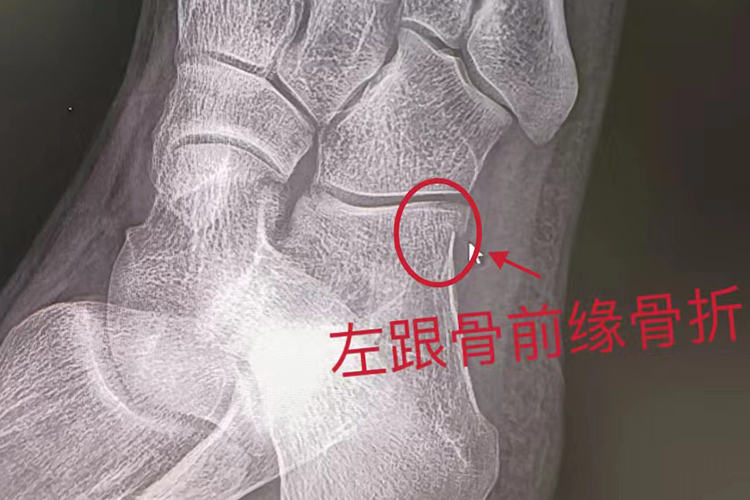

左跟骨前缘骨折会表现为足纵弓塌陷,跖屈的力量及足纵弓的弹簧作用减弱等,多由传达暴力造成,需及时就医治疗。

左跟骨前缘骨折后常有足纵弓塌陷,结节关节角减小、消失或成负角,影响足纵弓后部,跖屈的力量及足纵弓的弹簧作用减弱。局部还会有肿胀、充血的情况,患者自觉有剧烈的疼痛。

左跟骨前缘骨折多由传达暴力造成,如从高处坠下或跳下时,足跟部先着地,身体重力从距骨下传至跟骨,地面的反作用力从跟骨负重点上传至跟骨体,使跟骨被压缩或劈开,亦有少数因跟腱牵拉而致撕脱骨折者。

左跟骨前缘骨折应及时到医院就诊,重点是恢复跟距关节的对位关系和结节关节角,并注意矫正跟骨体增宽。对无移位的骨折,可仅外敷活血化瘀、消肿止痛的中药,并加压包扎制动,如双柏散、跌打镇痛膏等,3-4周后逐渐练功负重。有移位的骨折应尽可能复位满意,方法包括手法整复外固定、跟骨结节牵引复位固定、钢针撬拨复位固定等。